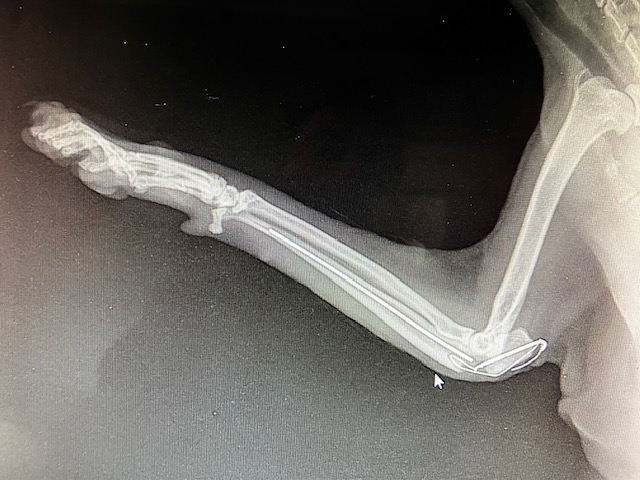

La zone de Fracture s’est écartée, la broche semble pliée, la fracture est instable et ne cicatrise pas correctement. La tension sur cette zone, sur l’olécrane, par la flexion des muscles brachiaux, exercent une forte traction, lors de flexion du coude. Ceci est aggravé par l’activité soutenue de cette jeune chatte. Nous décidons de reposer un pansement – attelle en attendant de ré-intervenir chirurgicalement.

Effectivement, quelques jours plus tard, la propriétaire signale que la chatte boîte fortement sans appui. Nouvelle radiographie : Rupture de l’implant. Sous la tension et la force de traction, la broche métallique, ainsi que le cerclage complémentaire qui devait s’opposer à la force de traction, ont cassé. Il faut reprendre la chirurgie.